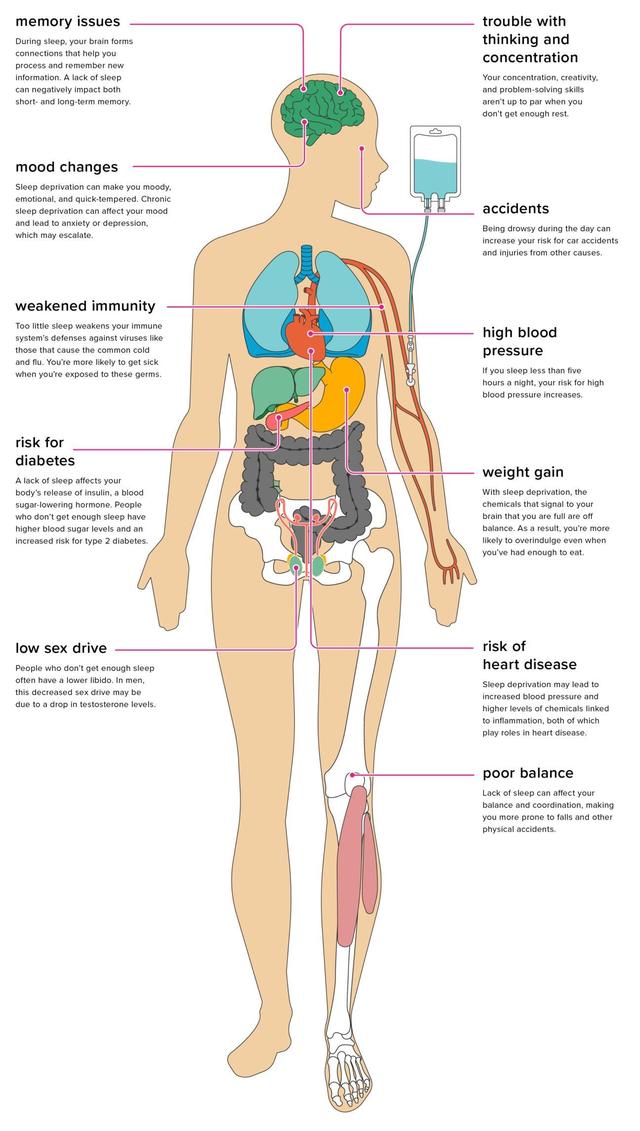

一晩中寝返りを打ったり、早朝にベッドに入ったりしたことがあるとしたら、翌日の気分はどうだろうか?たいていの人は、疲れて無気力になり、不機嫌になり、機嫌が悪くなるだろう。たまには、体が睡眠不足を補ってくれることもあるが、その効果はほとんどない。慢性的な睡眠不足(睡眠時間7時間未満)や質の低下(目が覚めやすい、夢を見過ぎる)は、健康に悪影響を及ぼし、さまざまな病気を誘発することさえある。睡眠不足はエネルギーを消耗させ、健康を危険にさらす。科学的研究によると、睡眠不足は体重増加から免疫力の低下など、多くの健康問題に関連している。

要するに、睡眠不足が続くか、睡眠の質が低下することによって引き起こされるのが睡眠不足であり、成人の通常の睡眠スケジュールは一晩あたり7~9時間と推奨されている。定期的に7時間未満の睡眠しかとれないと、やがて健康が損なわれ、全身に影響を及ぼします。睡眠不足は、夜更かしや不眠症、根本的な睡眠障害によって引き起こされることがある。

あなたの身体が最適に機能するためには、空気や食べ物が必要なのと同じように、睡眠が必要なのだ。睡眠中、身体は自然治癒力を高め、化学的バランスを回復する。脳は新しい思考のつながりを確立し、記憶の保持を助ける。

十分な睡眠がとれないと、脳や体のシステムが正常に働かず、生活の質も著しく低下する。慢性的な睡眠不足は早期死亡のリスクを高める。

I. 中枢神経系(脳)

中枢神経系は身体の主要な情報伝達機関であり、適切な機能を維持するためには睡眠が必要であるが、慢性的な睡眠不足は身体への情報伝達と処理の方法を乱す可能性がある。

- 睡眠中、脳の神経細胞(ニューロン)間に経路が形成され、学習した新しい情報を記憶するのに役立つ。睡眠不足は脳を疲弊させ、記憶力を低下させるため、年をとるとアルツハイマー病のリスクが高まる。

- 睡眠不足が続くと、集中力が低下したり、新しいことを覚えるのが難しくなったりする。また、体からの信号が遅れ、体の協調性が低下し、事故のリスクが高まる可能性もある。

- 睡眠不足は精神力や感情状態にも悪影響を及ぼし、焦りや気分の落ち込みを感じたり、判断力や創造力にも影響を及ぼす可能性がある。

- 睡眠不足が長く続くと、幻覚を見たり、ありもしないものを見たり聞いたりすることがある。睡眠不足は躁病の引き金にもなる。その他の心理的リスクは以下の通り:衝動的な行動、不安、抑うつ、パラノイア。

- 慢性的な睡眠不足は、日中に居眠りをしたり、気づかないうちに数秒間眠ってしまったりすることがある。居眠りは自分ではコントロールできず、運転中であれば非常に危険である。仕事で重機を操作しているときに居眠りをすれば、簡単に事故につながる。

免疫システム

睡眠時、免疫系は抗体やサイトカインといった感染防御物質を分泌する。身体はこれらの物質を使って、細菌やウイルスなどの外敵の侵入を撃退する。サイトカインも睡眠を助け、免疫系をより効果的に病気から体を守るようにします。十分な睡眠がとれていないと、免疫システムの正常な働きを妨げる可能性があります。もし慢性的な睡眠不足が続くと、身体は外敵から身を守ることができなくなり、病気からの回復に時間がかかるようになるかもしれない。この調査によると慢性的な睡眠不足は、高血圧、糖尿病、心臓病などの慢性疾患のリスクも高める。。

呼吸器系

消化器系

- 食べ過ぎと運動不足に加えてね。睡眠不足もまた、太りすぎや肥満の危険因子である。睡眠は、空腹感と満腹感をコントロールする2つのホルモン、レプチンと空腹ホルモンの分泌に影響を与える。

- レプチンは脳に十分食べたことを伝える。十分な睡眠がとれないと、脳はレプチンを低下させ、食欲増進ホルモンである空腹ホルモンを上昇させる。これらのホルモンの変化により、夜に間食をしたり、夜に食べ過ぎたりする人がいる理由が説明できる。

- また、睡眠不足が続くと、疲労感が強すぎて運動が続かなくなることもあります。運動量が減ると、カロリーが十分に消費されず、筋肉量も増えないため、体重が増えやすくなります。

- インスリンは血糖値を下げる働きがあり、このような乱れは糖尿病や肥満の原因となる。

V. 循環器系

- 睡眠は、血糖値、血圧、炎症レベルに影響を与えるプロセスなど、心臓血管系に影響を与える。睡眠はまた、血管や心臓を修復する身体の能力にも重要な役割を果たしている。

- 睡眠不足の人は心血管疾患にかかりやすい。睡眠不足は心臓発作や脳卒中のリスクを高めるという研究結果がある。

内分泌系

ホルモンの分泌は睡眠リズムに依存しており、睡眠不足や夜中の覚醒はホルモン分泌プロセスに影響を与える。

- 睡眠不足は、特に子供や青少年の成長ホルモンの分泌に影響を与える可能性がある。成長ホルモンは、成長機能に加えて、体の筋肉を成長させ、細胞や組織を修復する働きもある。